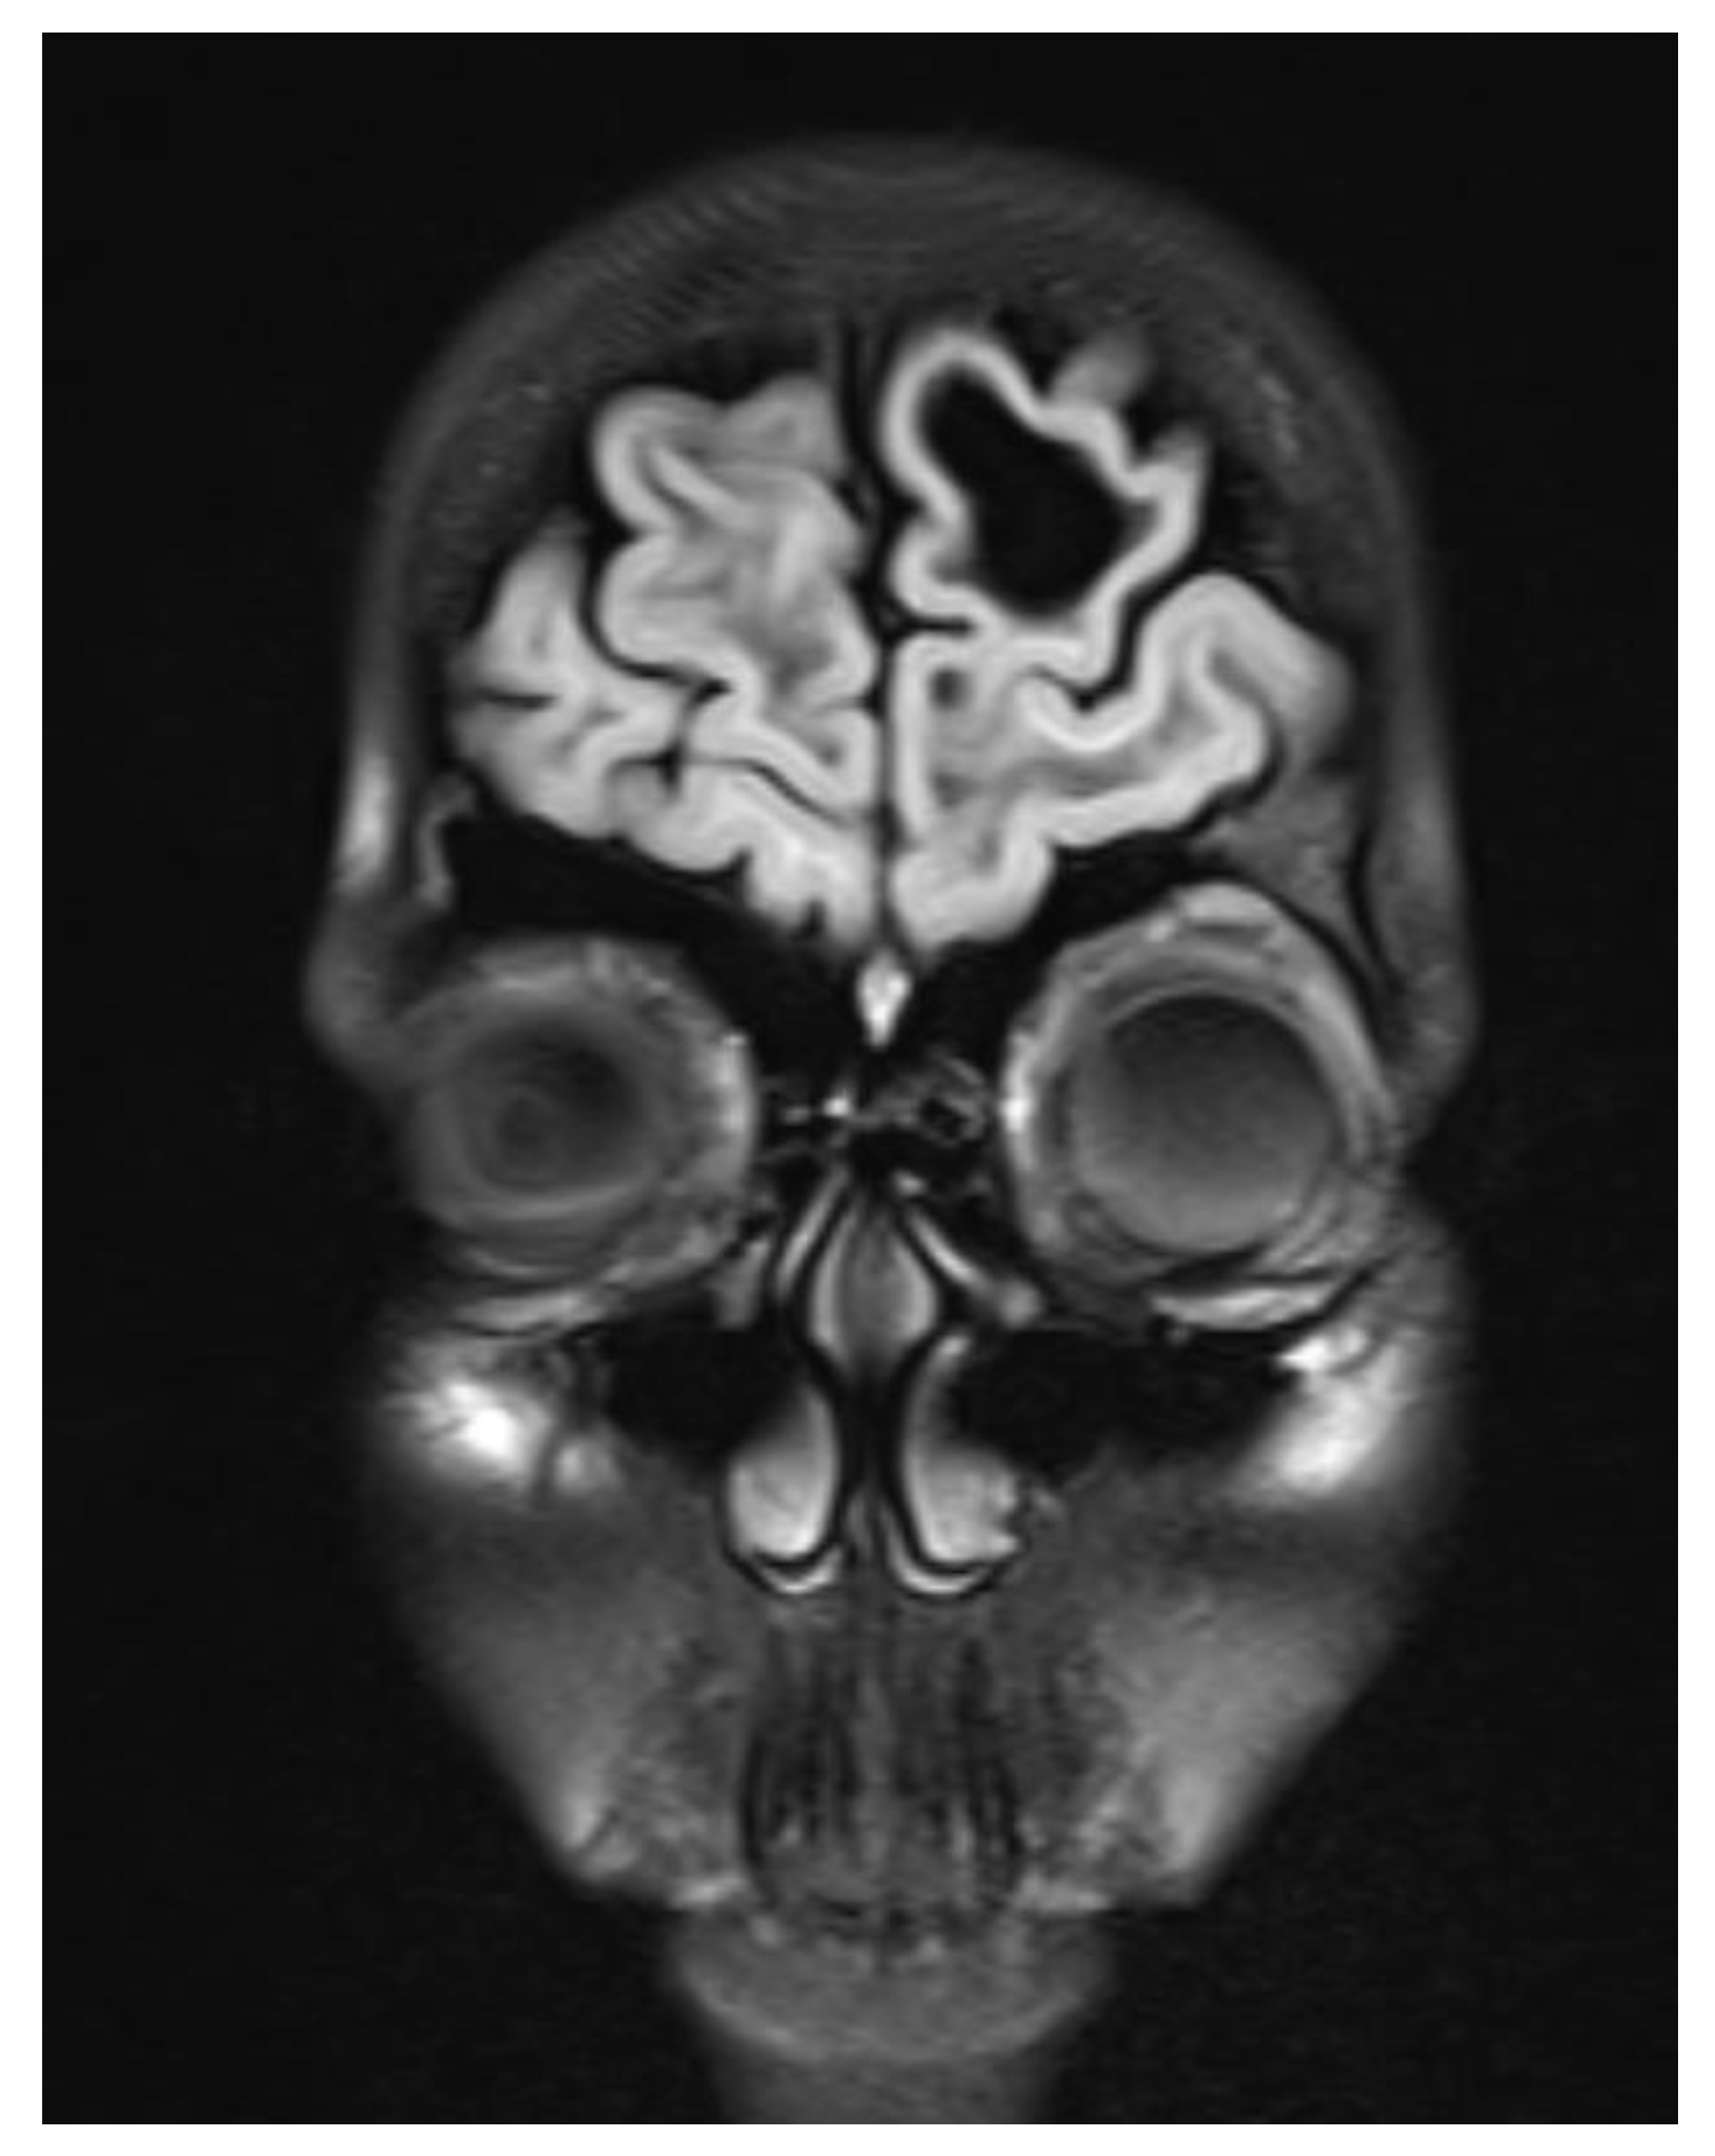

A contrast-enhanced MRI of the brain was performed, bilateral symmetrical diffuse abnormal T2WI/FLAIR hyperintensity involving the subcortical and periventricular deep white matter of bilateral cerebral hemispheres and corpus callosum with areas of diffuse restriction in bilateral centrum semi-ovale restriction, subcortical cysts, and cerebral atrophy were seen with possibility of Megalencephalic leukoencephalopathy with subcortical cysts also known as Van der knap disease. Post-contrast imaging showed normal enhancement, ruling out vascular abnormalities or abnormal enhancement patterns.

Figure 1. Coronal Flair image showing Bilateral symmetric white matter hyperintensity.

The clinical and radiological findings were consistent with megalencephalic leukoencephalopathy with subcortical cysts, also known as Van der Knaap disease.